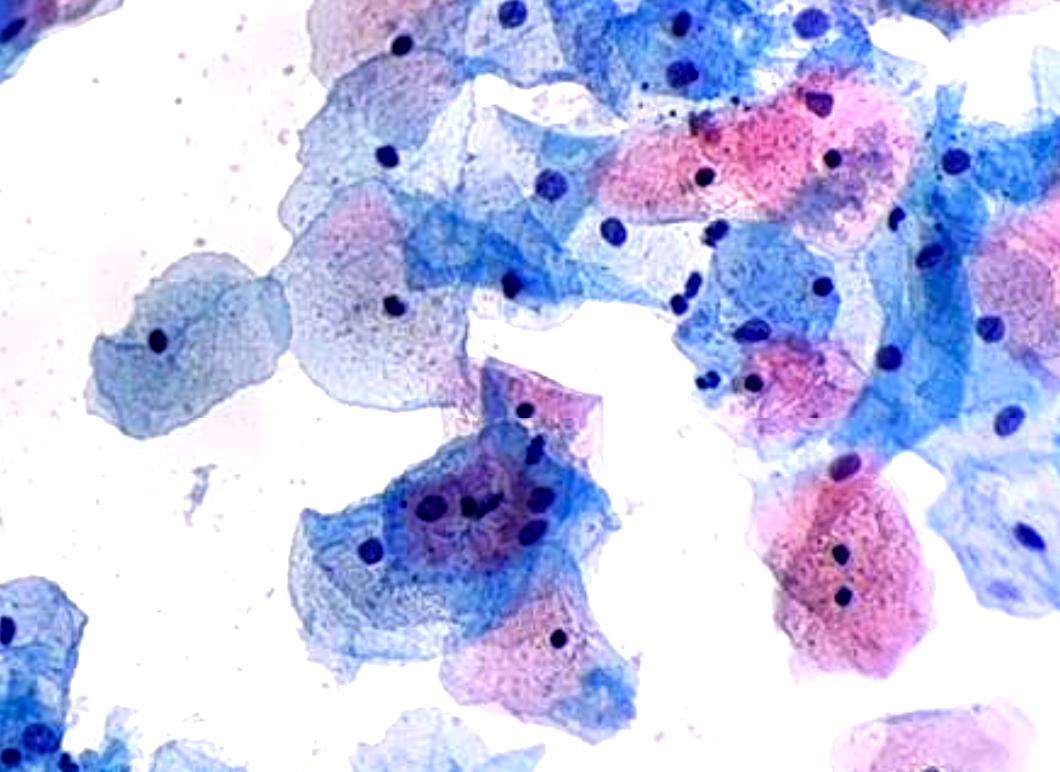

Pap Smear

AI-assisted cervical cancer screening with Bethesda classification system integration (beta version)